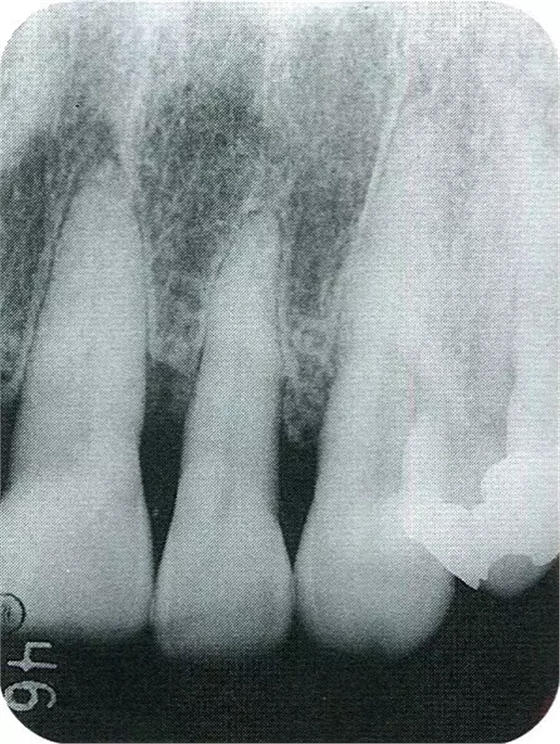

▲圖7-6再翻瓣半年之后的狀態(tài)。探診無出血,獲得了附著齦。

▲圖7-7術(shù)前,術(shù)后的x片。確認(rèn)出現(xiàn)骨再生,牙槽嵴硬線。